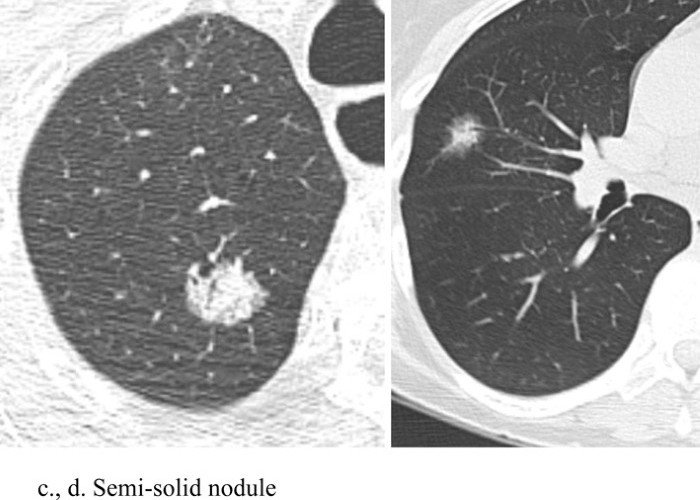

Chụp CLVT liều thấp cho phép xác định các nốt phổi bằng cách sử dụng liều bức xạ thấp nhất có thể. Điều này có thể thực hiện được thông qua việc sử dụng dòng điện và điện áp thấp hơn. Thử nghiệm tầm soát phổi Quốc gia (National Lung Screening Trial-NLST) đã thực hiện giảm liều bức xạ thông qua giảm dòng điện, với điện áp đỉnh là 120 kVp (140 kVp cho những BN béo), cường độ dòng điện từ 40 mA hoặc thấp hơn. Tùy thuộc vào máy chụp CLVT, liều hiệu quả trung bình là 1,4 milliSievert (mSv). Quá trình chụp CLVT được thực hiện trong thì hít vào mà không sử dụng chất cản quang tĩnh mạch. Hình ảnh chụp CLVT liều thấp trong chẩn đoán sớm UTP bao gồm: Nốt mờ đặc, nốt mờ bán đặc và hình ảnh nốt kính mờ (Hình 1), trong đó nốt mờ là hình ảnh hay gặp nhất [5, 6].

Hình 1: Nốt mờ đặc (a, b), bán đặc (c ,d) và nốt kính mờ (e, f).

Nguồn: Chiles C. (2014) [6].